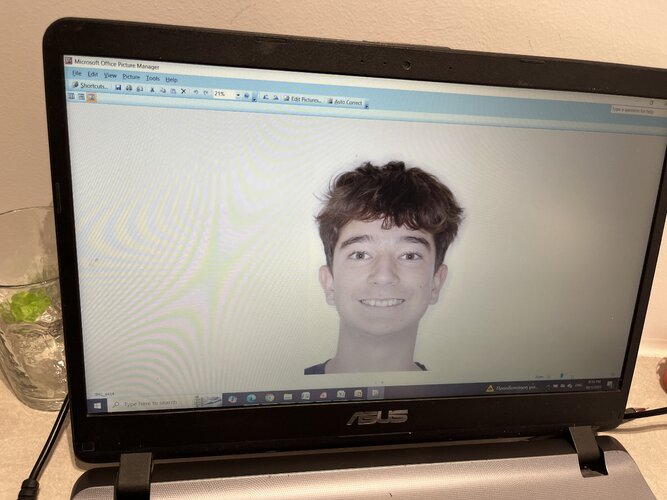

Important to note that my maxilla wasn’t downward grown until braces and headgear I am still 16 and upward thumb pressure is is not really doing anything much (I also had to fix my skeletal issue with my palate because my ortho only did tooth expansion instead of marpe/sarpe (aka breathing issues)